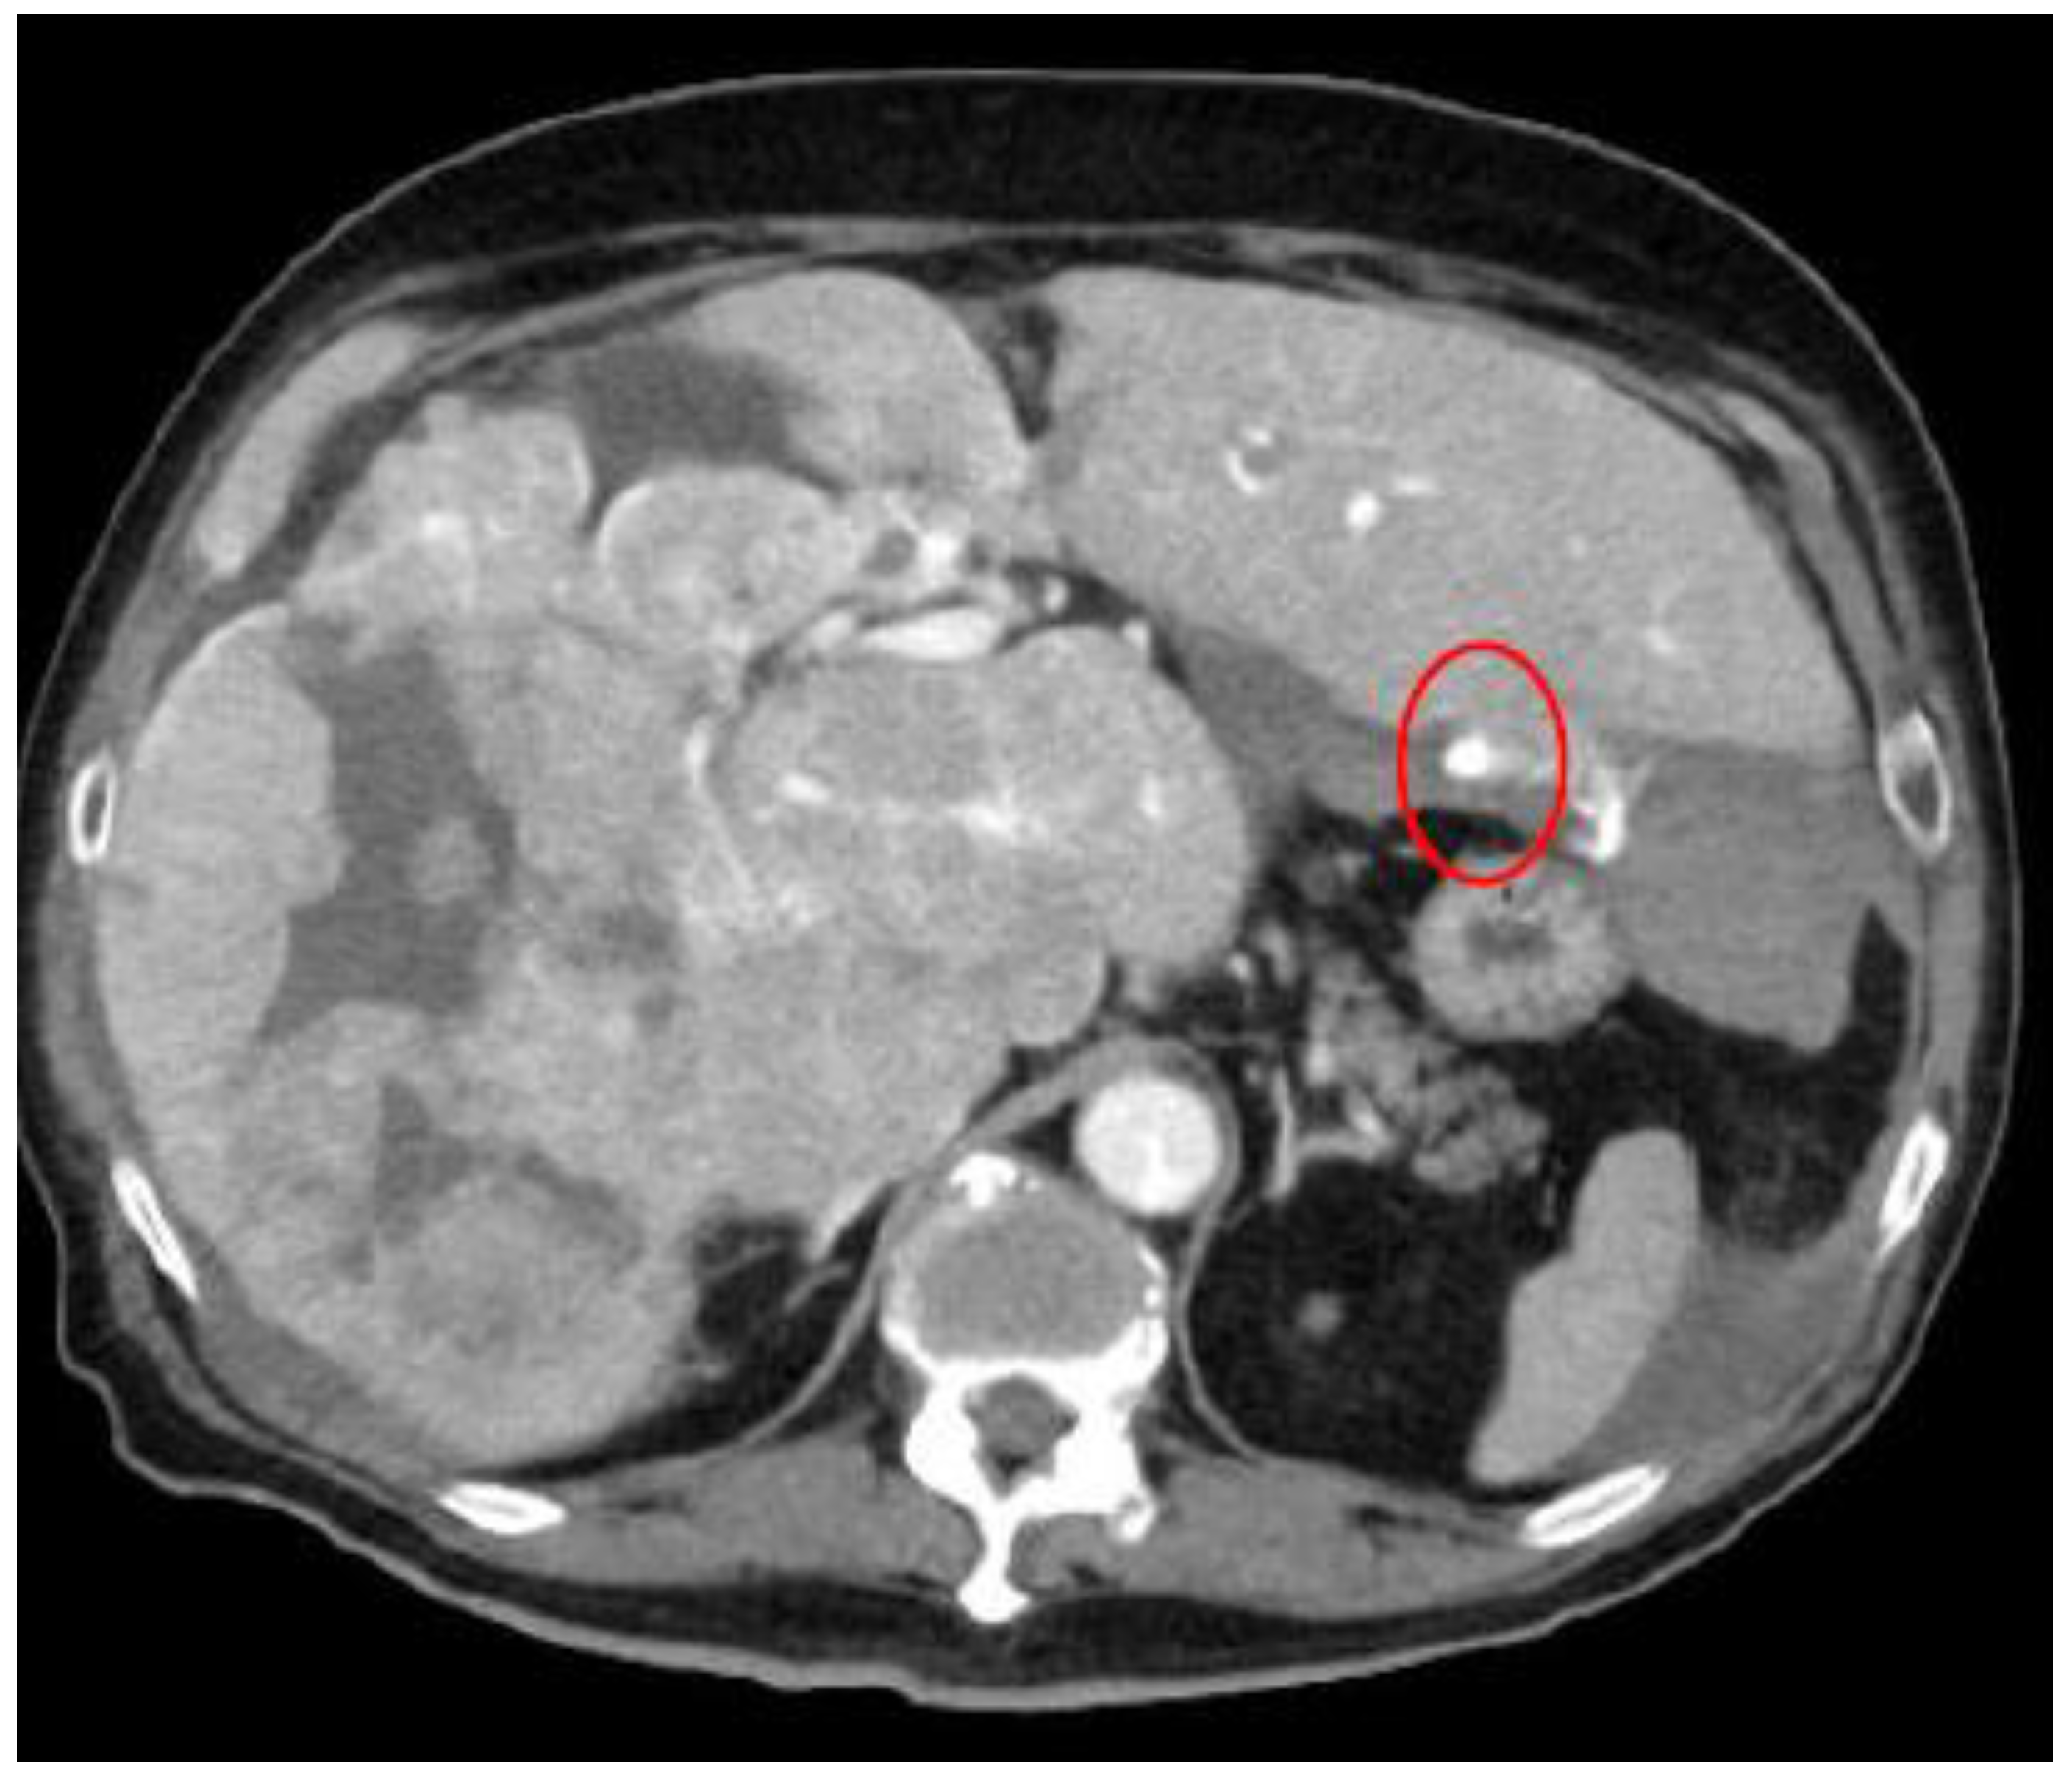

Additionally, Figure 6 delineates the locations of extravasation detected in a patient’s lung cancer as visualized on CT images. Specifically, in panel (b), one of the feeding arteries of the tumor (the right bronchial arterial) is depicted. Identifying the responsible vessel on CT proved challenging, leading to the decision to embolize this artery. The patient had previously experienced hemoptysis prior to initiating chemotherapy.